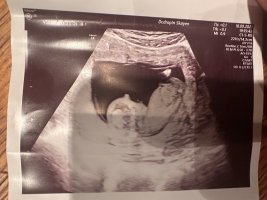

Litt uklart bilde, men tipper gutt. Det jeg tror er nub har litt høy vinkel til å være jente. Har du flere bilder i andre vinkler?Lyst til å gjette?Bilde fra uke 13+0. Vet ikke om nuben synes så godt men

Litt uklart bilde, men tipper gutt. Det jeg tror er nub har litt høy vinkel til å være jente. Har du flere bilder i andre vinkler?

Tipper guttNoen som klarer tyde nub her? 12+5